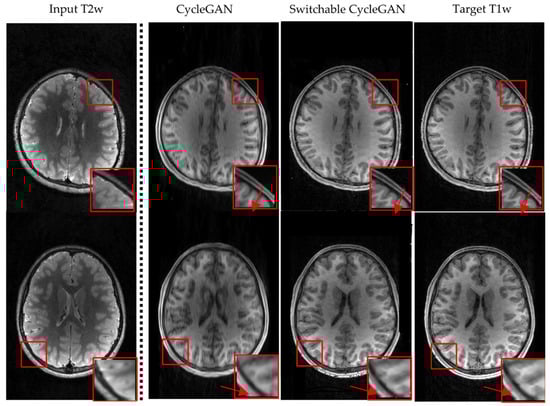

3.2. Visualization